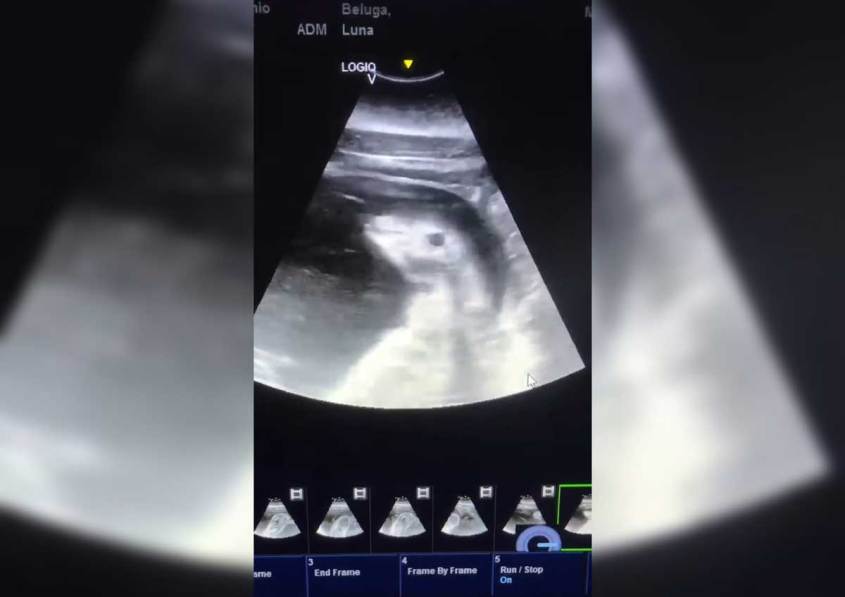

It’s the reminder no one needed: SeaWorld is beyond out of touch. The abusement park company took to social media on January 11 to flex its speciesist muscles, posting a sonogram depicting the unborn baby of Luna, a beluga whale who has been confined at SeaWorld San Antonio for more than two decades.

The publicity stunt is seemingly a vain attempt to attract new visitors to its park in Texas (where Luna resides in a cramped tank), making it clear that SeaWorld has forgotten (or perhaps just doesn’t care) that no one wants to buy tickets to a place that dooms newborns to a lifetime of exploitation.

Such cringe-worthy abuse is not new to Luna. In order for her to conceive her first calf, workers sexually abused her by forcibly impregnating her with the sperm of Nanuq.

Despite rejecting her calf, Alta (who was one of the first belugas conceived through artificial insemination), Luna gave birth to two more babies—and now she’s been impregnated again, possibly by forced insemination.